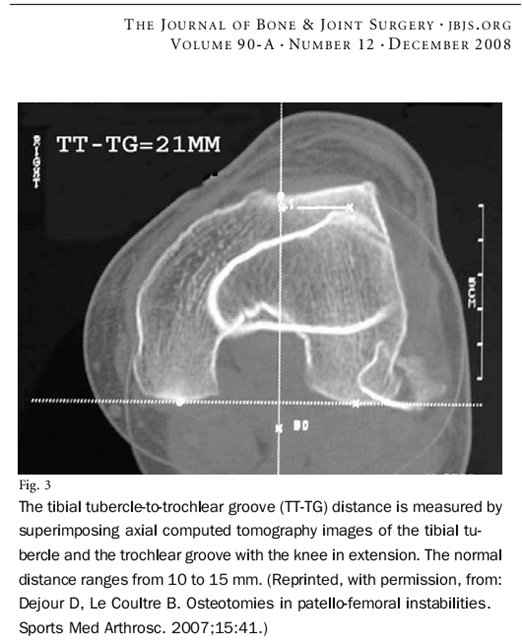

Кто-нибудь использует в своей практике такой метод диагностики? Как технически делать это? Позволяет ли сам аппарат КТ делать такую склейку, либо ее можно делать самому на компьютере?

Полагаю данный индекс важным в выборе тактики операции.